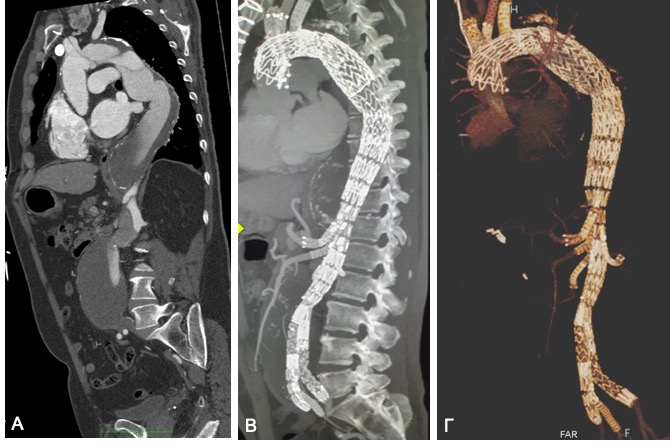

Προεγχειρητική αξονική αγγειογραφία του ανευρύσματος του αορτικού τόξου και της θωρακικής αορτής, στην οποία φαίνεται το διαχωριστικό ανεύρυσμα (A). Μετεγχειρητική αξονική αγγειογραφία μετά την πλήρως ενδαγγειακή αποκατάστασή του (B,Γ).